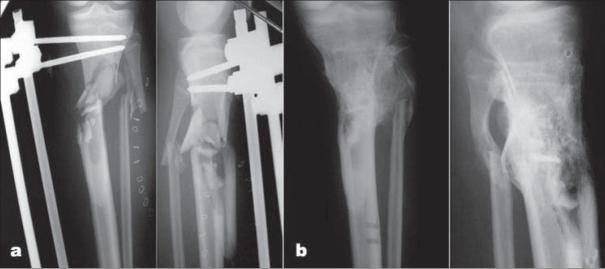

The Taylor spatial frame (TSF) is a modern multiplanar external fixator that combines the ease of application and computer accuracy in the reduction of fractures. A retrospective review of our prospective TSF database for the use of this device for treating open tibial fractures in pediatric, adolescent, and adult patients was carried out to determine the effectiveness and complications of TSF in the treatment of these fractures.

Nineteen male patients with open tibial fractures were included. Of these fractures, 10 were Gustilo Type II, five were Gustilo Type IIIA (two had delayed primary closure and three had split thickness skin grafting), and four were Gustilo Type IIIB (all had rotational flaps). Twelve of our patients presented immediately to the emergency room, and the remaining seven cases presented at a mean of 3 months (range, 2.2-4.5 months) after the initial injury. The fractures were located in proximal third (n=1), proximal/middle junction (n=2), middle third (n=3), middle/distal junction (n=8), distal third (n=3), and segmental fractures (n=2). Patients were of an average age of 26 years (range, 6-45years). Mean duration of follow-up was 3.5 years.

RESULTS

All fractures healed over a mean of 25 weeks (range, 9-46 weeks). All were able to participate in the activities of daily living without any difficulty and most were involved in sports during the last follow-up. Postoperative complications included pin tract infection in 12 patients.

The TSF is an effective definitive method of open tibial fracture care with the advantage of early mobilization, ease of soft tissue management through gradual fracture reduction, and the ability to postoperatively manipulate the fracture into excellent alignment.